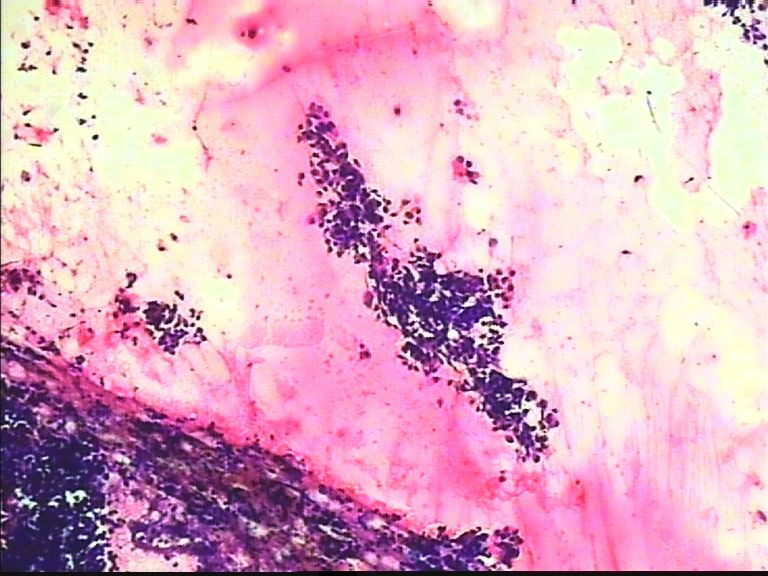

38岁 乳腺肿瘤 女

考虑癌:图18细胞核形式不规则,染色质粗块状,可见核仁.

乳腺癌

乳腺癌。

浸润导管癌

好像重复了。浸润性导管 癌。

从所给图看恶性是没什么问题!染色有点过,染色质结构欠清晰;关于细胞学判断浸润的问题我想应综合来判断,如单个细胞的异形性,细胞整体弥散情况,细胞微粒结构以及间质成分等等,个人的认识也起到一定因素,细针穿刺中最常规用的还是--导管癌。